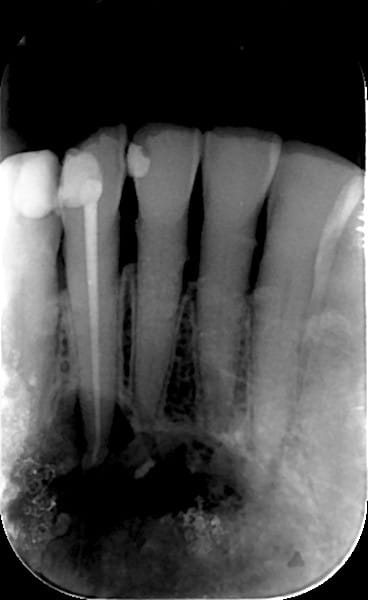

Elle a été envoyé, par son dentiste, à l’hôpital pour un scanner, et l'interne qui l'a vue, lui a dit qu'elle n'avait rien, et qu'il fallait juste que son dentiste refasse éventuellement le traitement canalaire de sa 42.

l'image de la première radio de la deuxième serie.... bizarre...

ça peut cristalliser le contenu d'un kyste ? :D

Pas besoin d'un chir maxillo pour çà, la pano déforme énormément. Le risque de fracture est assez peu important car l'os basal n'est pas atteint. Un chir oral ou un MBD s'en sortira sans pb, "suffit" d'ouvrir par 2 incisions de décharge en avant des trous mentonniers et décollement du lambeau, on tombe sur la bête directement, en général çà n'est retenu que par l'apex en cause que l'on sectionne et hop anapath de principe et on referme. Le plus long c'est de suturer correctement. LBFA030, 73,21€, mdr...

Mais endo canine d'abord!